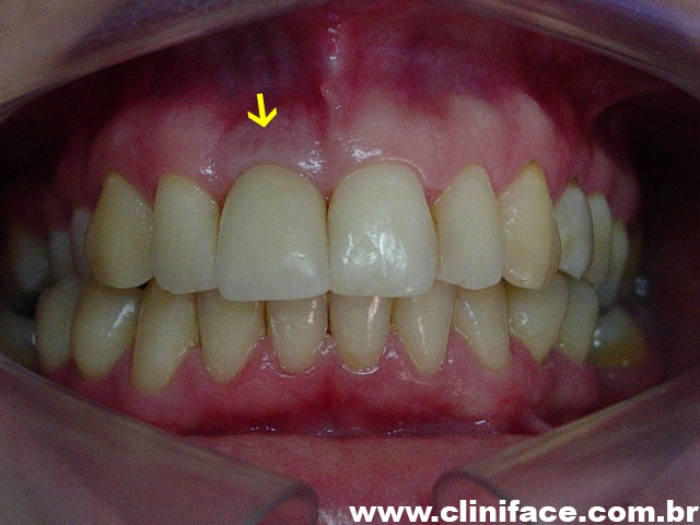

Imagem final do caso terminado em setembro de 2006

Sorriso final